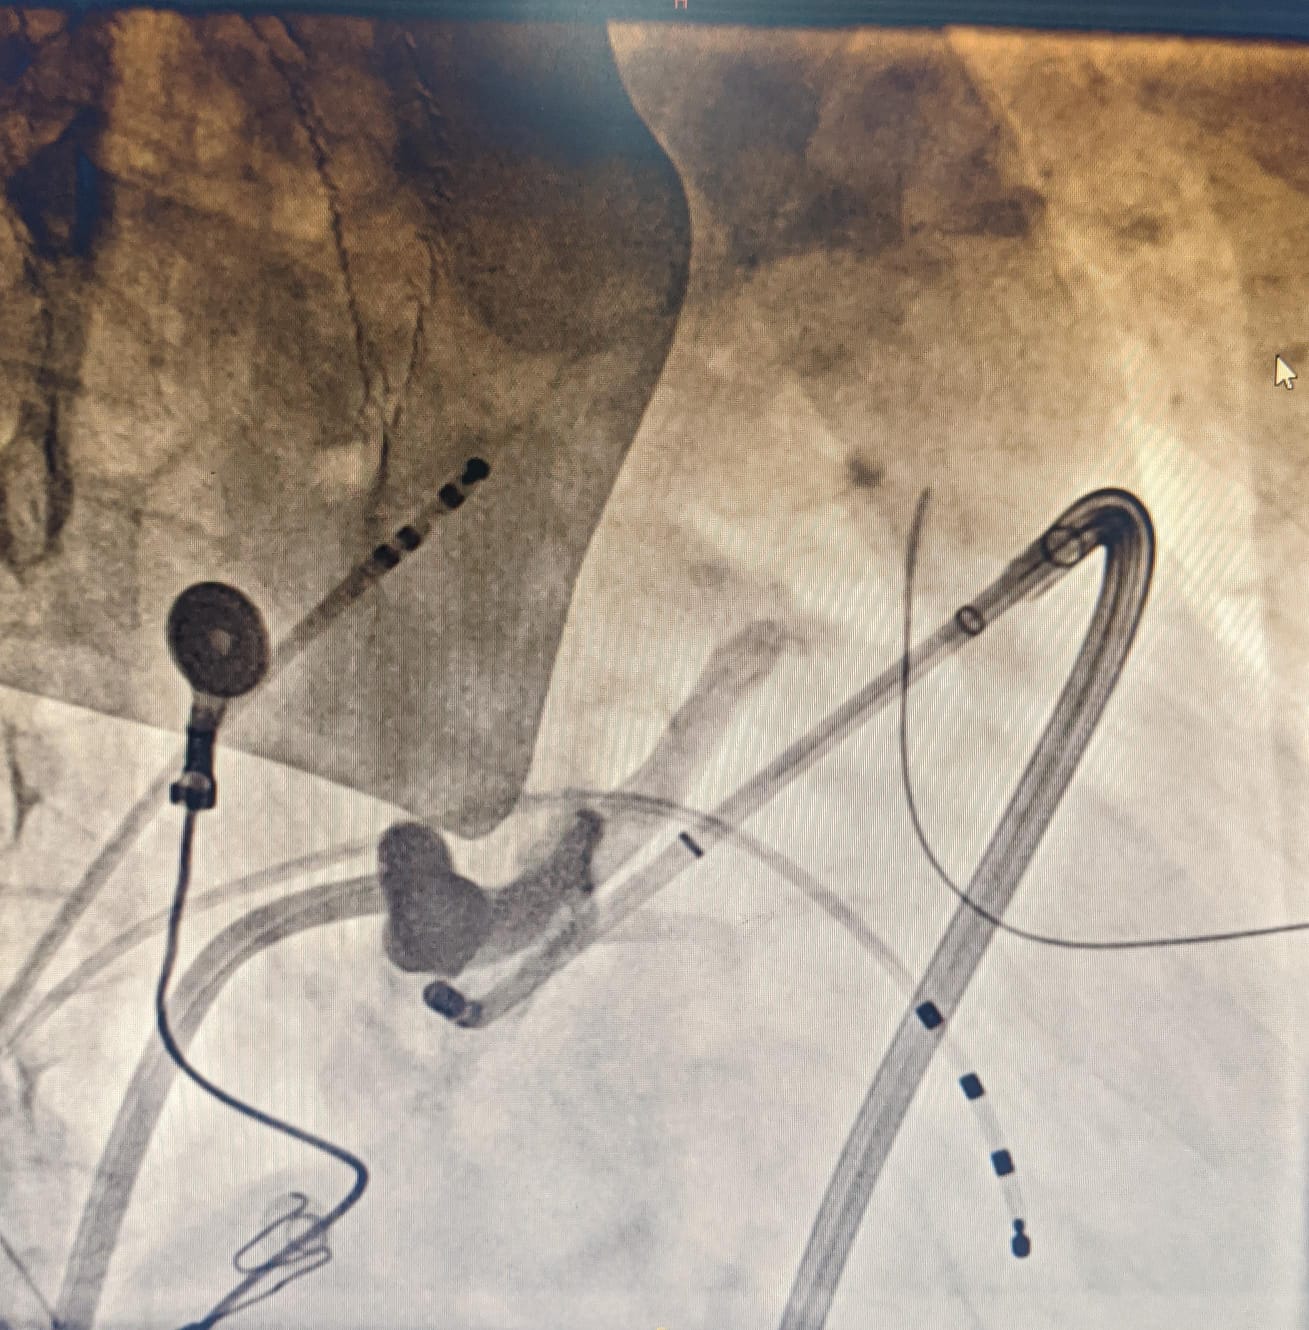

Mapping in diverticulum

diverticulum.jpg

med_lat_div.jpg

signals.jpg

Mapping in diverticulum - CSE potential most important

div_schematic.jpg

Selvaraj RJ et al. Radiofrequency ablation of posteroseptal accessory pathways associated with coronary sinus diverticula. J Interv Card Electrophysiol. 2016 Nov;47(2):253-259. doi: 10.1007/s10840-016-0113-x.